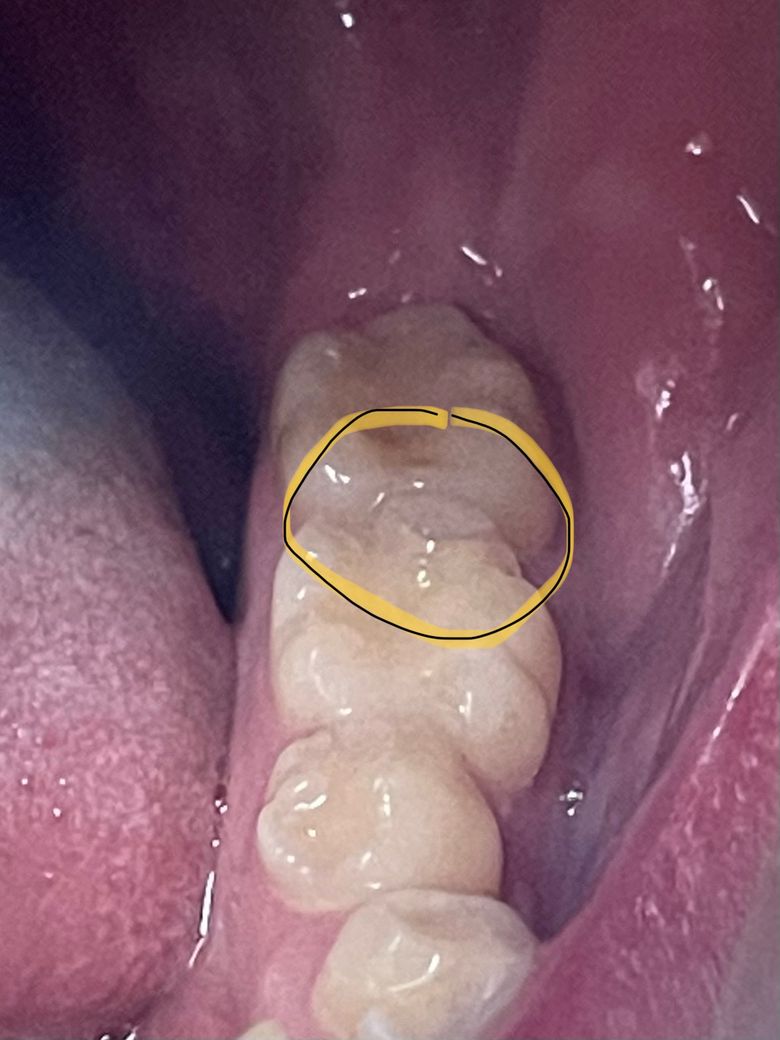

(사진첨부) 어금니 옆에 매꾼 게 깨져서 떨어지려고 하는데 다시 메꿀 수 있나요?

한 곳에서 진료봤더니 크라운이 좋다고 하시는데

다시 메꿀 순 없는 건가요? ㅜ 크라운 하면 지르코니아 하고 싶은데 가격에서 주춤하네요 ㅎㅎ..

저부위는 힘을 많이 받는 부위라서 단순히 메꾸면 계속 떨어질 가능성이 높습니다. 인레이나 크라운치료를 하셔야될것같습니다.

큰어금니는 음식물을 씹어먹기 위한 치아이므로 크라운을 하시는 것이 좋습니다.

계속 떨어질겁니다.